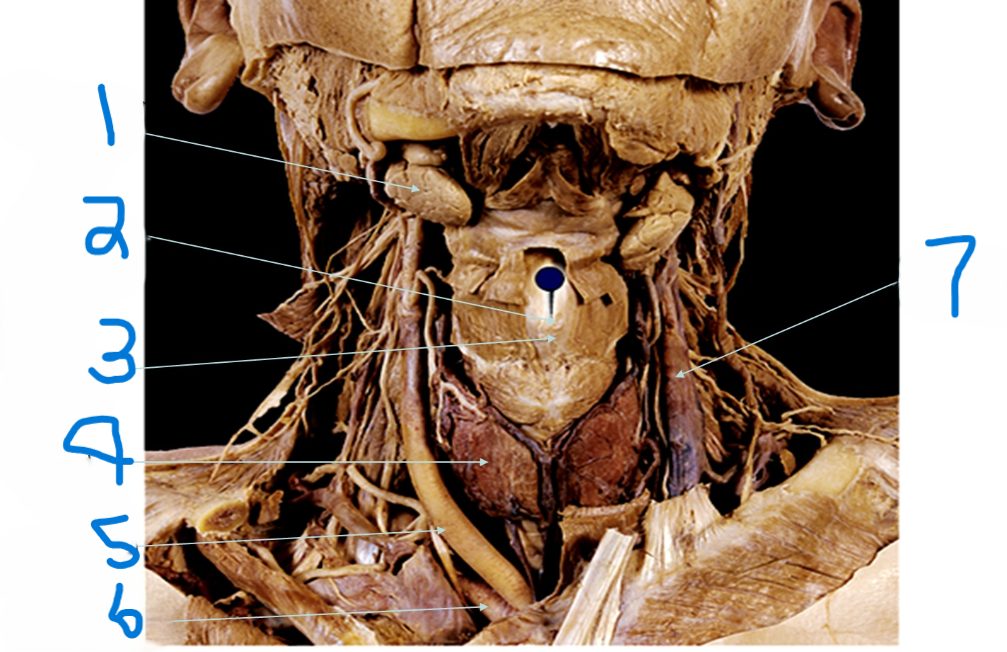

What is depicted by #1

Laryngeal Prominence (adams apple)

What is depicted by #2

Thyroid cartilage

What is depicted by #3

Thyroid gland

What is depicted by #4

Right common carotid artery

What is depicted by #5

Right subclavia artery

What is depicted by #6

Left internal jugular vein

What is depicted by #7